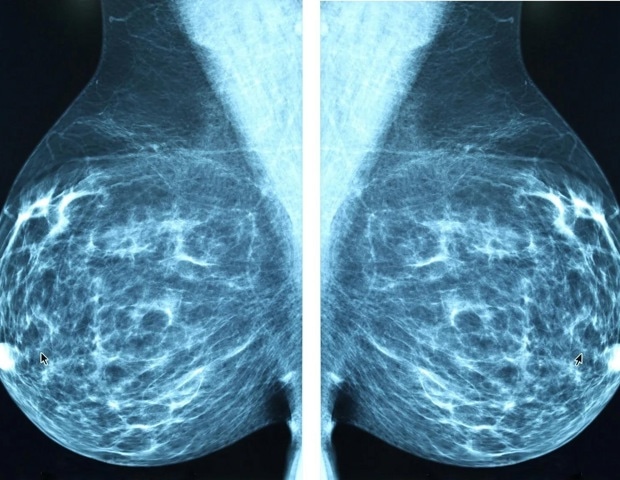

Новые национальные тенденции подчеркивают рост заболеваемости раком молочной железы у молодых женщин, что побуждает к переоценке возрастных порогов скрининга и стратегии стратификации риска.

Доктор Дестоунис вместе со своей коллегой Андреа Л. Арьено, бакалавром наук, руководителем исследований в EWBC, попыталась выявить рак, диагностированный с 2014 по 2024 год в общественной практике, состоящей из семи амбулаторных учреждений в радиусе 200 миль в западном регионе Нью-Йорка. Они выявили все виды рака молочной железы в возрасте от 18 до 49 лет. группа и собрала информацию из отчетов о клинических визуализациях.

«Мы специально собирали подробную информацию о том, как рак был обнаружен (скрининг или диагностика), типе рака и других характеристиках опухоли», - сказал доктор Дестоунис. «Мы исключили случаи, которые не были первичным раком молочной железы. Мы проанализировали тенденции с течением времени по возрастным подгруппам, методу обнаружения и биологии опухолей. Это помогло нам определить, как рак молочной железы проявляется у этой группы пациентов, как часто он встречается и какие типы опухолей обнаруживаются».

Всего 1799 случаев рака молочной железы было диагностировано у 1290 женщин в возрасте от 18 до 49 лет. Ежегодно в этой группе диагностируется рак молочной железы от 145 до 196, средний возраст постановки диагноза 42,6 года (диапазон 23–49 лет). Из них 731 (41%) были обнаружены при скрининге, а 1068 (59%) - при диагностической оценке. Было зарегистрировано 1451 случай инвазивного рака (80,7%) и 347 (19,3%) случаев неинвазивного рака.

«Большинство этих видов рака были инвазивными, то есть они могли распространяться за пределы груди, и многие из них были агрессивными типами, особенно у женщин до 40 лет», - сказал доктор Дестунис. «тройной негативный», форма рака молочной железы, которую труднее лечить, поскольку она не реагирует на обычные гормональные методы лечения».

Несмотря на то, что женщины в возрасте до 50 лет составляли от 21% до 25% пациентов, проходивших ежегодное обследование, на их долю неизменно приходился один из каждых четырех случаев рака молочной железы, обнаруживаемых каждый год.

«Это поразительно, потому что показывает, что молодые женщины не только несут стабильную и значительную долю бремени рака молочной железы, но и опухоли часто являются биологически агрессивными", - сказала она. "Такая комбинация - устойчивая заболеваемость плюс непропорционально агрессивная биология - напрямую бросает вызов возрастным ограничениям для скрининга и усиливает аргументы в пользу более ранних, ориентированных на риск подходов скрининга".